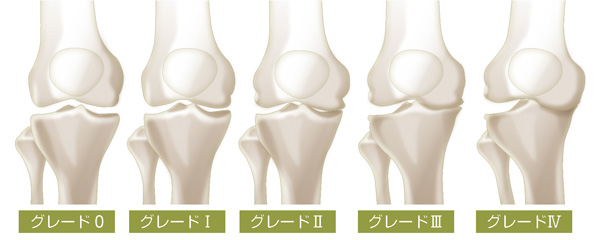

整形外科を受診したからといって、すぐ手術をすることはありません。整形外科ではレントゲンを撮り、KL分類という指標(グレード0~Ⅳ)に合わせて、進行具合を見極めます。軟骨がだいぶ減っているグレードⅢ・Ⅳでも痛くないと言われる方もいますので、グレードと痛みの両方を見て治療法を考えていきます。

変形性膝関節症のKL分類